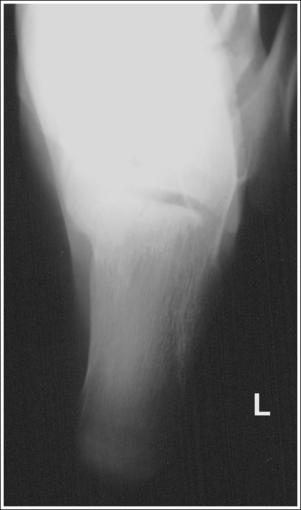

The ankle is demonstrated in an AP projection. The medial mortise (tibiotalar articulation) is open, and the distal tibia and talus are superimposed over the distal fibula by a small amount (0.125 inch [3 mm]), closing the lateral mortise (fibulotalar articulation).

• An AP projection of the ankle is obtained by positioning the patient supine on the image table, with the leg fully extended and the foot dorsiflexed until its long axis is placed in a vertical position (Figure 6-47). In this position, the intermalleolar line (imaginary line drawn between the medial and lateral malleoli) is at a 15- to 20-degree angle with the IR. The medial malleolus is positioned farther from the IR than the lateral malleolus.

• Detecting direction of ankle rotation. If the ankle was not positioned in an AP projection but is rotated laterally or medially, the medial mortise is obscured. When an AP ankle projection demonstrates a closed medial mortise, one can determine which way the patient's leg was rotated by evaluating the amount of tibia and talar superimposition of the fibula and the position of the medial malleolus. In external rotation, the tibia and talus demonstrate greater superimposition of the fibula and the posterior aspect of the medial malleolus (Figure 6-48) is situated medial to the anterior aspect (see Image 32). In internal rotation, the fibula is demonstrated without talar superimposition (see Image 33).

The tibiotalar joint space is open, and the tibia is demonstrated without foreshortening.

• The tibiotalar joint is open and the tibia is demonstrated without foreshortening if the patient's lower leg was positioned parallel with the IR and the central ray was centered at the level of the tibiotalar joint.

• Evaluating the openness of the tibiotalar joint. On an AP ankle projection, determine whether an open joint was obtained and whether the tibia is demonstrated without foreshortening by evaluating the anterior and posterior margins of the distal tibia. On an AP ankle projection with accurate positioning, the anterior margin is demonstrated approximately 0.125 inch (3 mm) proximally to the posterior margin (see Figure 6-48). If the proximal lower leg was elevated or the central ray was centered proximal to the tibiotalar joint, the anterior tibial margin is projected distally, resulting in a narrowed or obscured tibiotalar joint space (see Image 34). If the distal lower leg was elevated or the central ray was centered distal to the tibiotalar joint, the anterior tibial margin is projected more proximally to the posterior margin than on an AP ankle projection, expanding the tibiotalar joint space and demonstrating the tibial articulating surface (see Image 35).

The tibiotalar joint space is at the center of the exposure field. The distal fourth of the tibia and fibula, the talus, and the surrounding ankle soft tissue are included within the collimated field.

• To place the tibiotalar joint in the center of the image, center a perpendicular central ray to the ankle midway between the malleoli. The medial malleolus is located at the same level as the tibiotalar joint space. Open the longitudinal collimation to include the calcaneus and one fourth of the distal lower leg. Transverse collimation should be to within 0.5 inch (1.25 cm) of the ankle skin line.

The ankle was not placed in an AP projection. The medial mortise is obscured, the tibia and talus demonstrate increased superimposition of the fibula, and the posterior aspect of the medial malleolus is situated medial to the anterior aspect. The ankle was externally rotated.

The ankle was not placed in an AP projection. The fibula is demonstrated without talar superimposition. The ankle was internally rotated.

The tibiotalar joint is closed. The anterior tibial margin has been projected into the joint space. Either the proximal tibia was elevated because of knee flexion, or the central ray was centered proximal to the tibiotalar joint.

Extend the knee, lowering the proximal tibia until the lower leg is parallel with the IR, or center the central ray to the tibiotalar joint (located at the level of the medial malleolus).